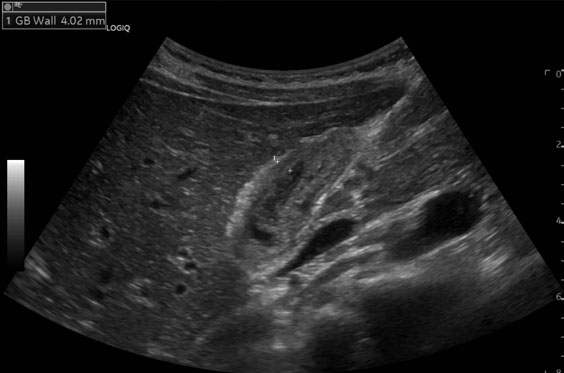

On physical exam, the patient had epigastric tenderness. Preoperative labs were notable for leukocytosis, hypoalbuminemia, direct hyperbilirubinemia (direct bilirubin of 2.8 mg/dL, total bilirubin of 2.9 mg/dL), elevated alkaline phosphatase, elevated aspartate aminotransferase, elevated alanine aminotransferase, and mildly elevated lipase. An abdominal ultrasound showed a thickened GB wall and a dilated common bile duct (CBD) (Figure 1). Due to suspicion of biliary tract disease, he underwent magnetic resonance cholangiopancreatography (MRCP), which showed a CBD diameter of 7.6 mm without evidence of choledocholithiasis or definitive evidence of cholecystitis (Figure 2). Because of concerns for a passed gallstone, he underwent inpatient laparoscopic cholecystectomy three days later.

Figure 2: Coronal view of the common bile duct with magnetic resonance cholangiopancreatography on patient admission. The common bile duct shows moderate dilation to 7.6 mm with some biliary sludge noted but no evidence of choledocholithiasis.